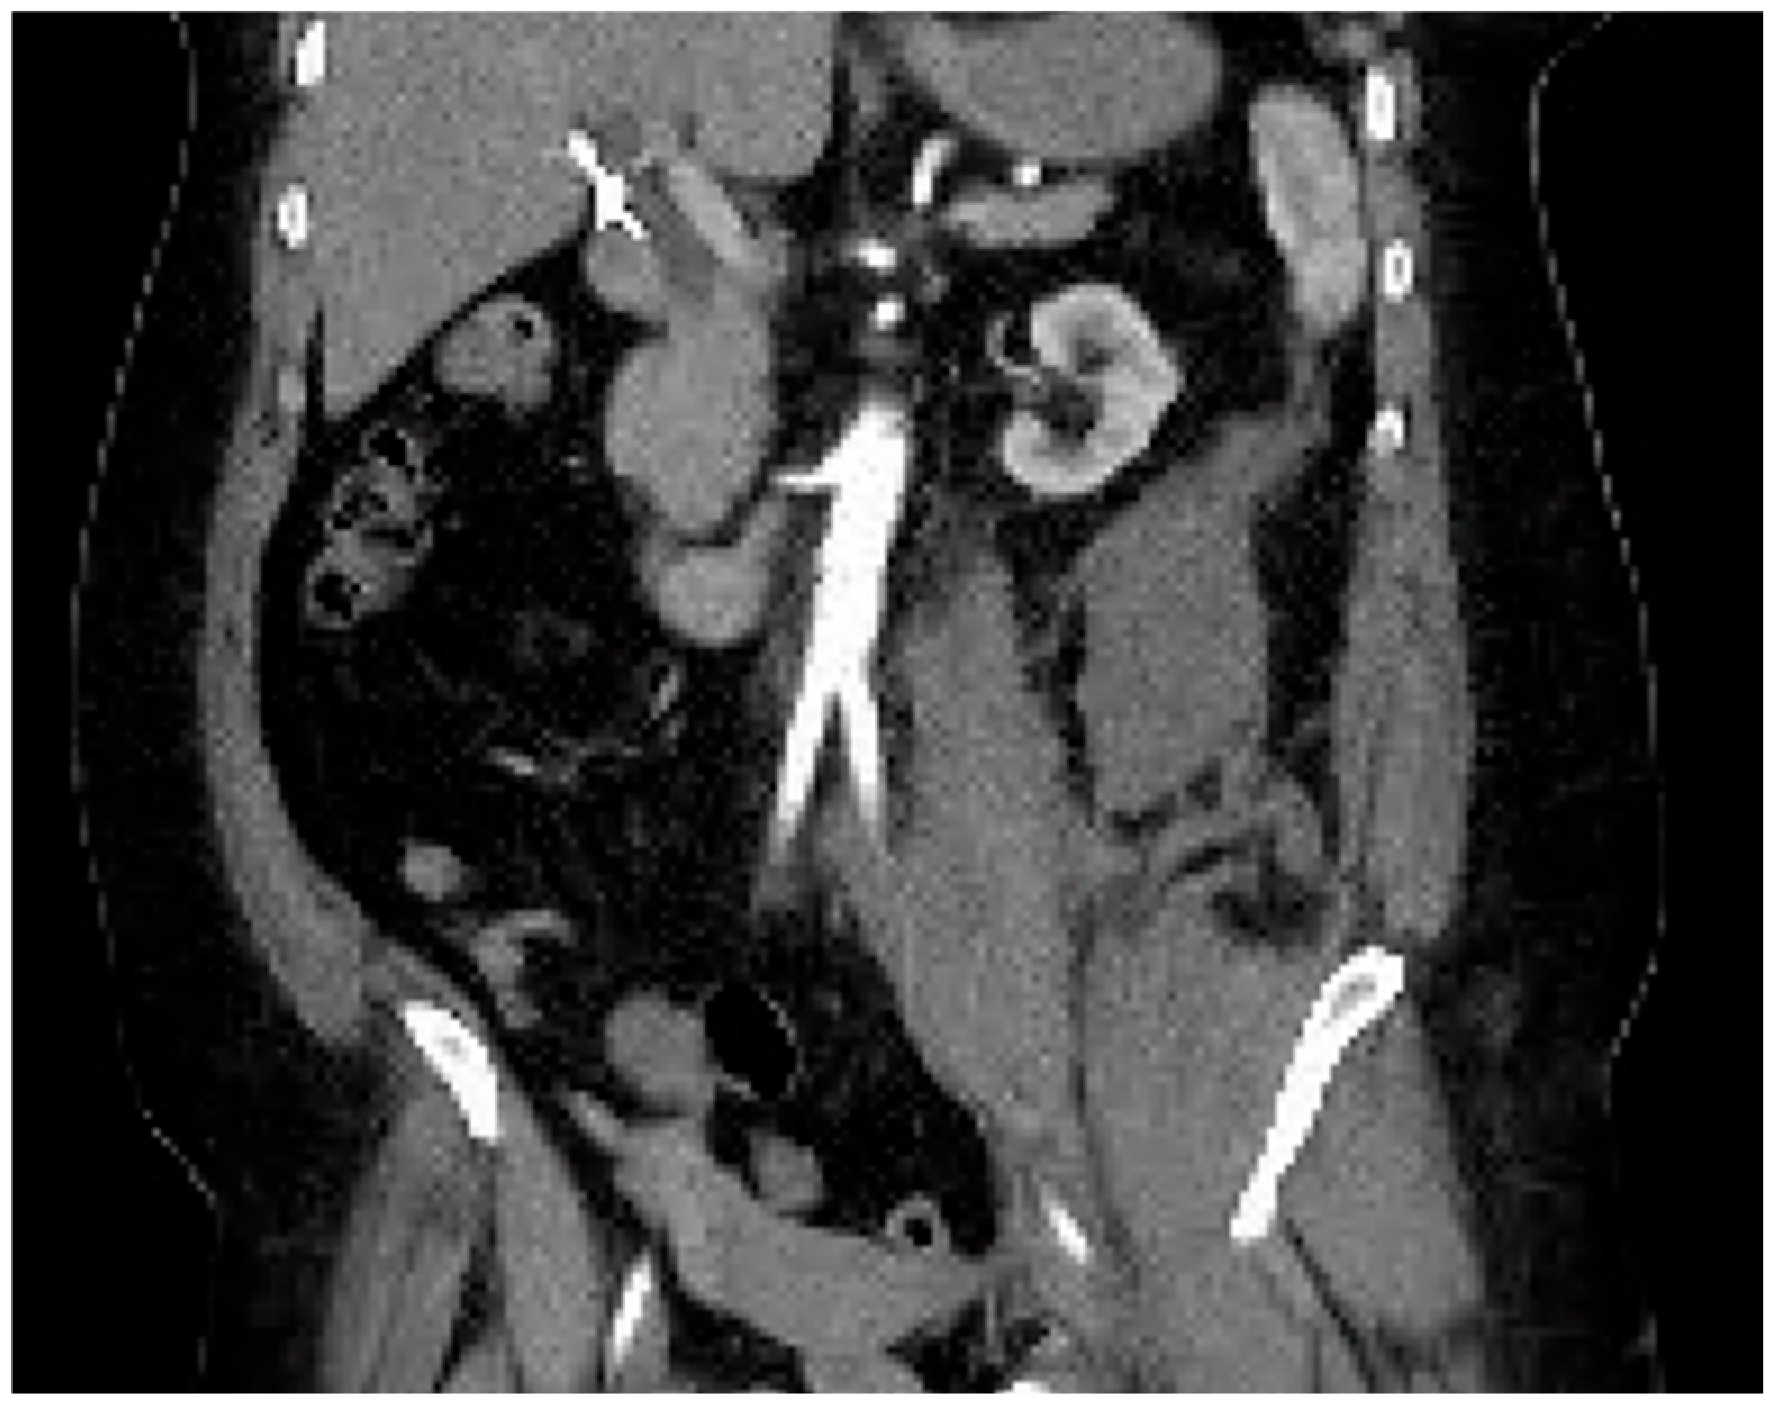

Computed tomography angiogram (CTA) protocol images are displayed below. Figure 1 and Figure 2 correspond to her state prior to tPA administration; notice the 100% occlusive aortic thrombus. Figure 3 and Figure 4 are post-tPA administration, demonstrating the fully restored aortic flow.

Figure 2. CTA in coronal view prior to tPA.

The patient’s only complaint was that both of her legs hurt and she could not feel them. On initial examination, the patient’s initial vital signs were as follows: blood pressure: 120/44; heart rate: 53; respiratory rate: 20; rectal temperature: 93.3 F. Her lower extremities showed bilateral petechiae and molting of the feet and were cold to the touch. Dorsalis pedis pulses and posterior tibialis pulses were unable to be palpated. These absent pulses were verified using bedside Doppler and color-flow ultrasound. The patient was immediately brought to imaging, and a CT angiogram of the aorta with a contrast protocol was performed to rule out dissection. CT imaging demonstrated an occlusion of the distal abdominal aorta (without dissection), with concurrent occlusion of the bilateral common iliac arteries.